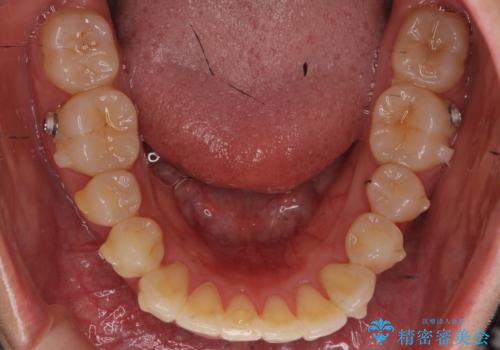

- 矯正装置

- インビザライン

上のワイヤー矯正を半年ほど行い反対咬合を改善してから、上下インビザライン治療を行いました。

下の前歯を中に入れるためにIPR(歯をわずかに削る処置)を行いました。

左上の反対咬合になっていた歯の頬側咬頭は、すでに削れて短くなっていましたがそのまま並べています。